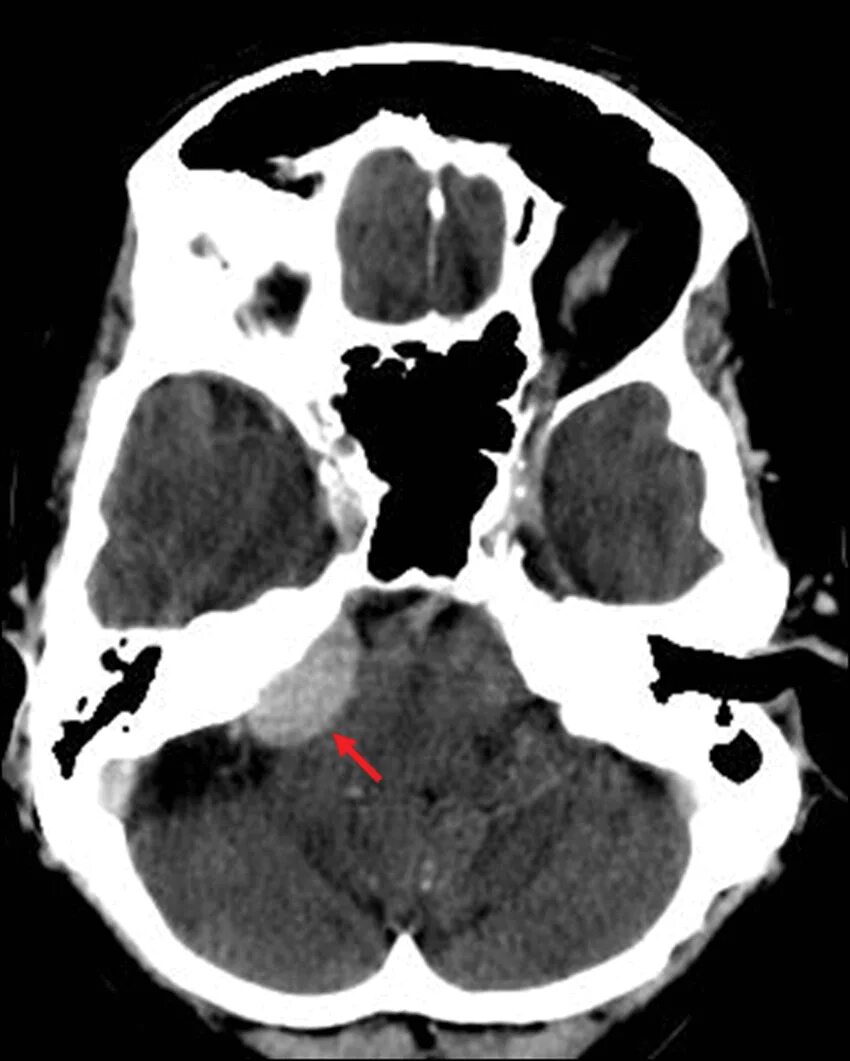

Мрт головного мозга мосто мозжечкового угла